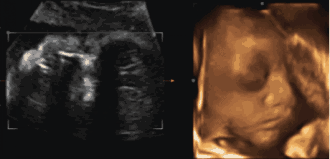

为了提前探寻这一“真相”

我们可以通过一个特别的仪式

在影像中让宝宝与爸爸妈妈提前相遇

感受宝宝与父母奇妙的连接

这一切,只需要选择四维彩超就可以啦

1、四维彩超最佳时间是孕24—26周。